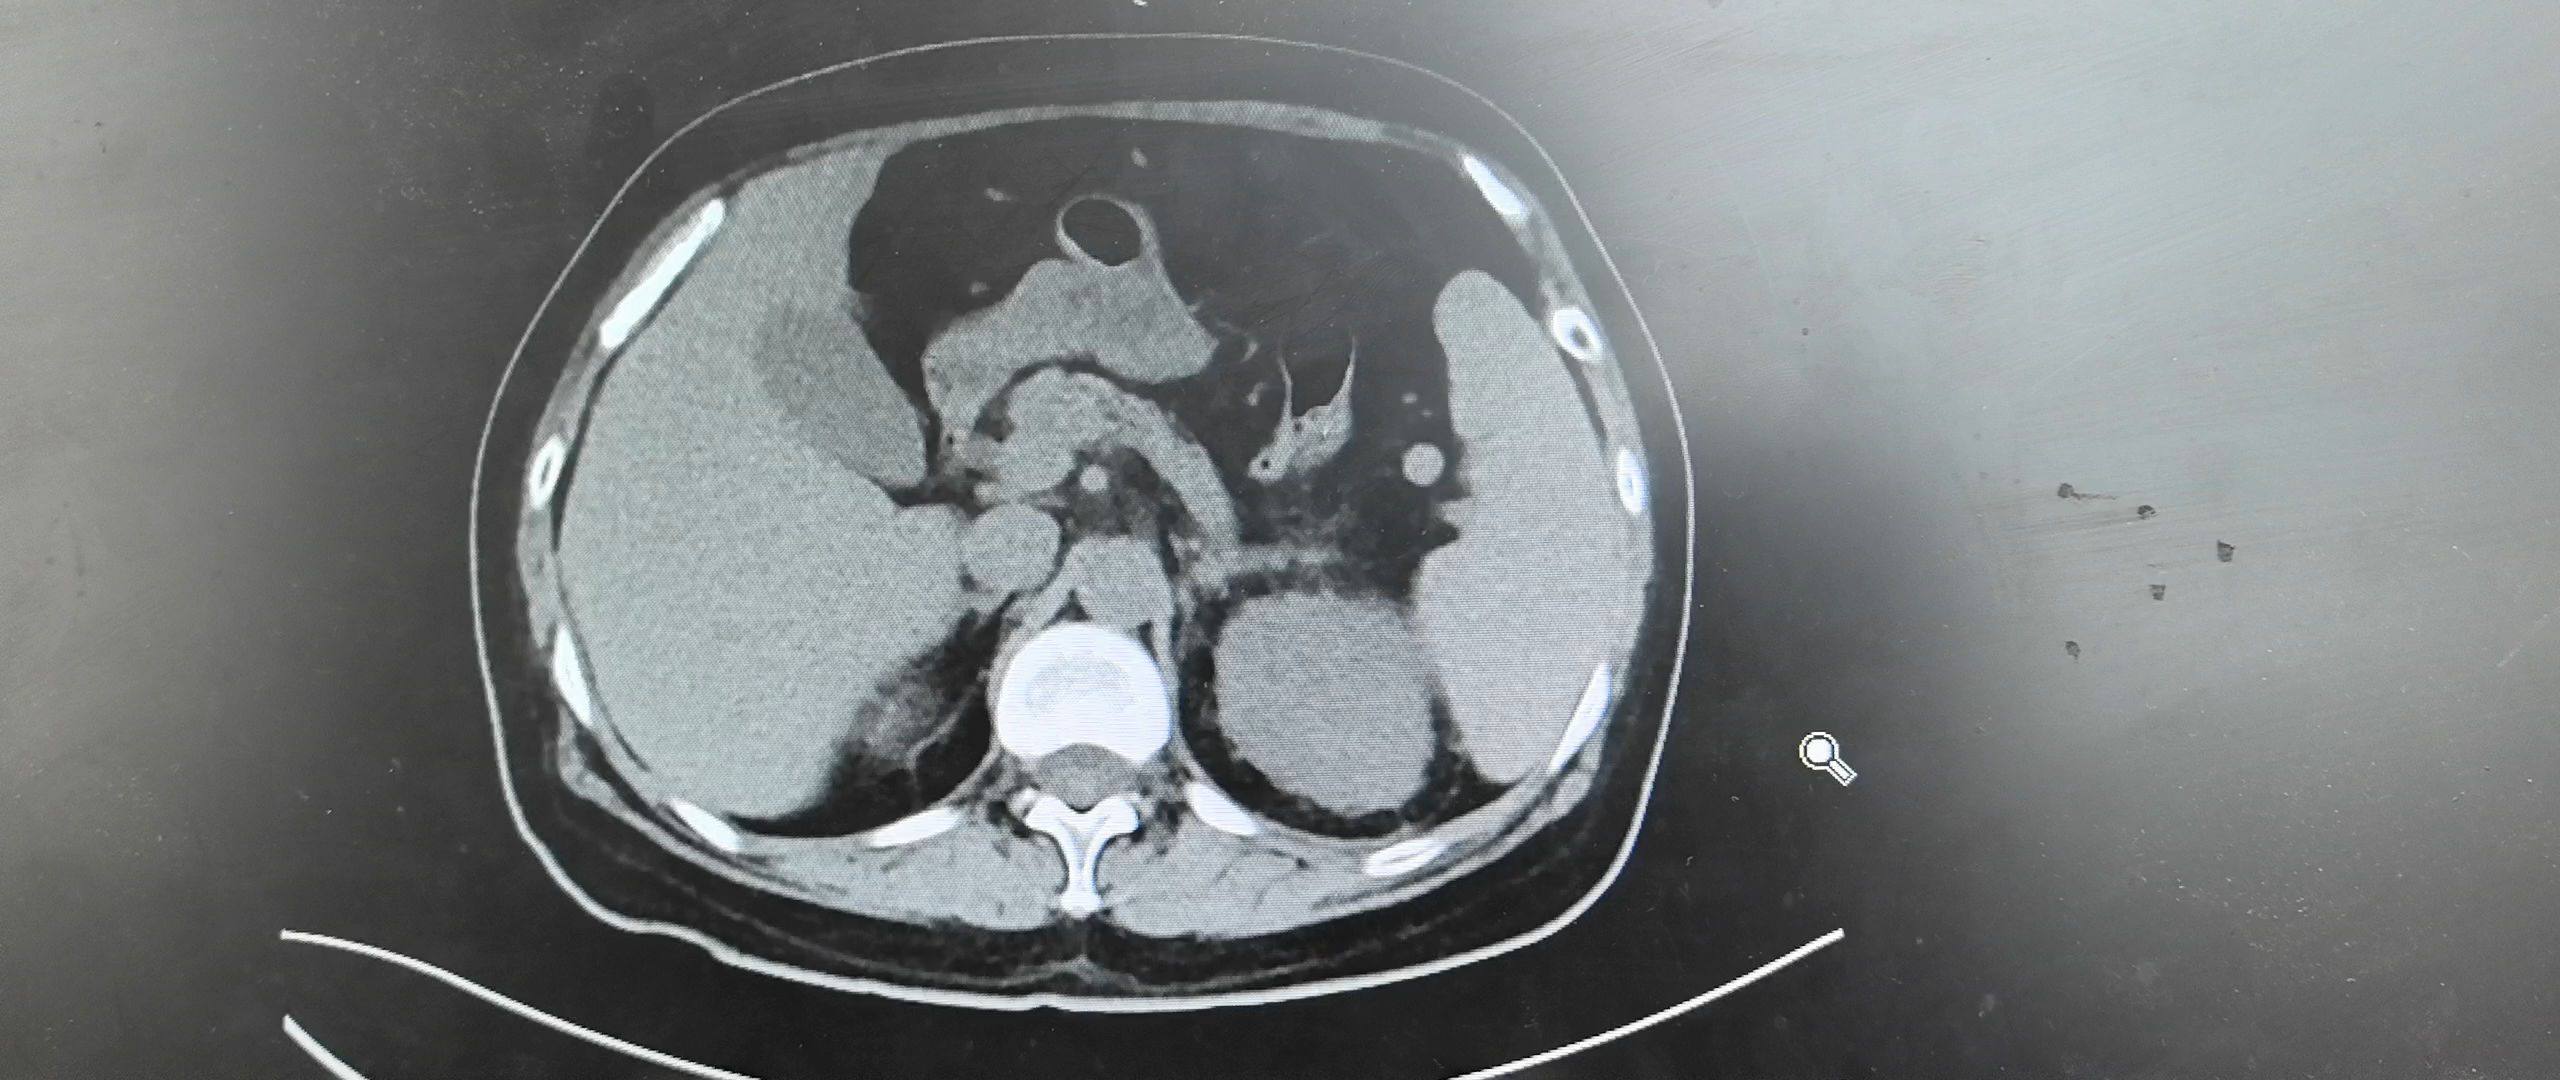

但是这件事也跟上级医师汇报过了,我想做个全腹CT看一看,但是一方面因为DRG付费原因,还有就是上级医师也说腹部彩超做过了,没有什么问题,你做啥做,到时候医保又让你反馈。此时我也很纠结,就跟病人家属说明了情况,目前感染源确实不明确,而且新发症状有腹痛,建议完善一个全腹CT看看,但是刚入院彩超没看出来东西,全腹CT也不一定能扫出来,与病人家属详细沟通后,同意完善全腹CT如下图:

患者血象越来越高,而且尿常规也明显异常,因为饮食欠佳,都出现酮症了,住院期间血糖监测一直还好没有超过13mmol/l,此时因为患者家属已同意行全腹CT检查,结果此时也已经出来了。

2025-05-06我院全腹CT